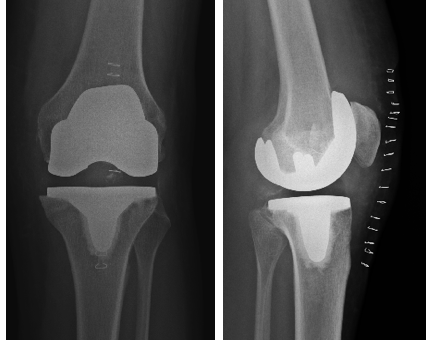

Abbildung 1 a–b:

a) Schematische Darstellung des Kniegelenkes (Fa. Aesculap)

b) Arthrose mit aufgefasertem Gelenkknorpel am Oberschenkel (Pathologisches Institut der Charité Berlin)